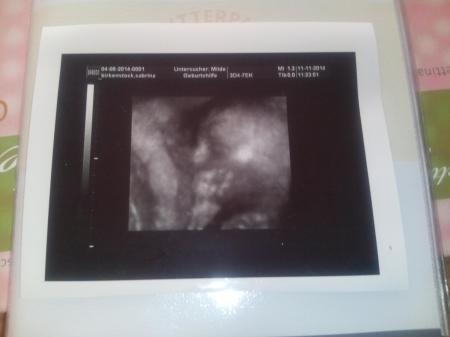

Das Krümel ist ca. 25 cm gross

Merkt man an den mächtigen Tritten